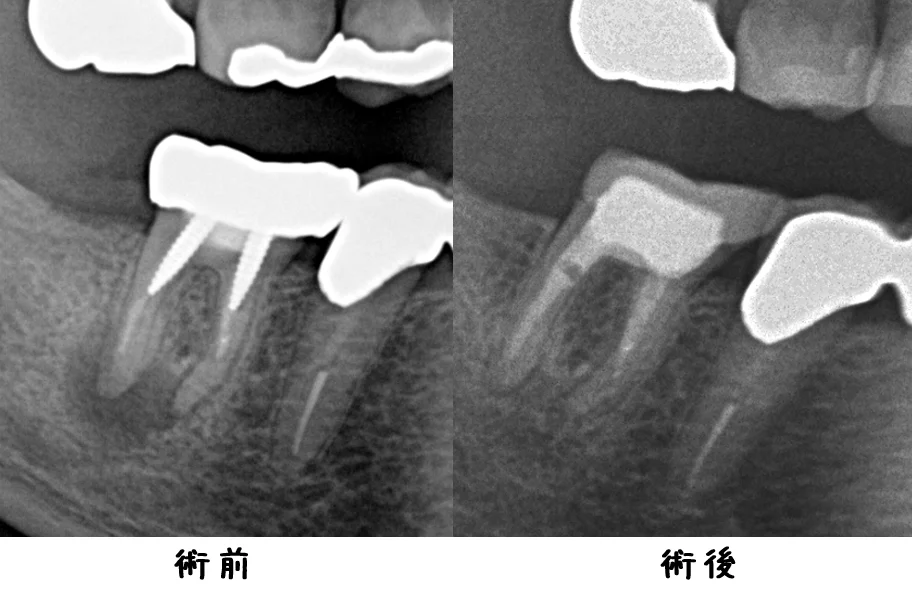

今回1年後の経過としてレントゲンを撮影させて頂いたのが、こちらです。

根の先の膿が完全に消えてくれたのが分かるかと思います。

入れたセラミックも適合良く入ってくれています。

治療を開始してからは痛みなどは一切出ずに、順調に過ごせているとのことでしたので、良かったです。

抜かないで済んでよかった~と喜んでいただき、幸いです。

ただ、予後が悪いことに変わりはありませんので、今後も定期的に診査させて頂くことになると思います。